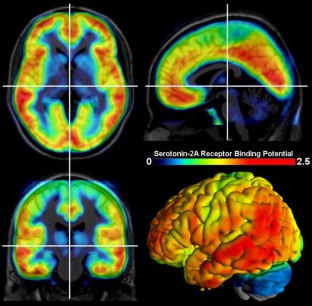

The serotonergic system is one of the most important modulatory neurotransmitter systems in the human brain. It plays a central role in major physiological processes and is implicated in a number of psychiatric disorders. Along with the dopaminergic system, it is also one of the phylogenetically oldest human neurotransmitter systems and one of the most diverse, with 14 different receptors identified up to this day, many of whose function remains to be understood. The system’s functioning is even more diverse than the number of its receptors, since each is implicated in a number of different processes. This review aims at illustrating the distribution and summarizing the main functions of the serotonin (5-hydroxytryptamin, 5-HT) receptors as well as the serotonin transporter (SERT, 5-HTT), the vesicular monoamine transporter 2, monoamine oxidase type A and 5-HT synthesis in the human brain. Recent advances in in vivo quantification of these different receptors and enzymes that are part of the serotonergic system using positron emission tomography are described.

Acknowledgments

We are grateful to Alexander Neumeister, Assoc. Prof., Mount Sinai School of Medicine and VA Connecticut Healthcare System, who provided 5-HT1B data for the figure. We thank the medical and technical teams of the Department of Psychiatry and Psychotherapy (S. Kasper, C. Spindelegger, P. Stein, M. Fink, U. Moser, E. Akimova, A. Hahn) and the PET Center at the Department of Nuclear Medicine (W. Wadsak, M. Mitterhauser, K. Kletter, R. Dudczak, G. Karanikas, L.-K. Mien, D. Häusler).